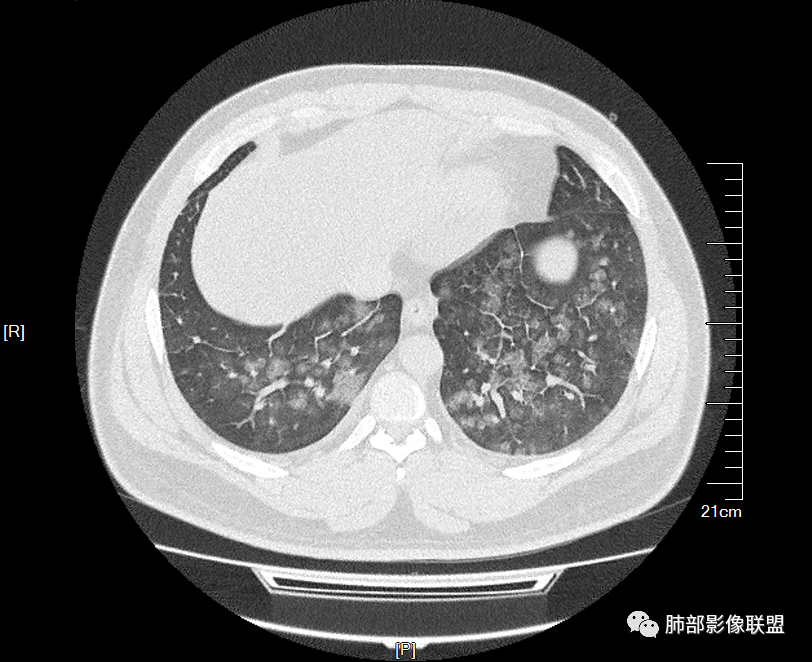

双肺多发弥漫性磨玻璃结节影,大小不一,形态不规则,部分融合,支气管未见明显扩张,部分血管束略增粗,叶裂胸膜增厚,临床有痛风,左足痛6天,考虑:1:痛风结节(一般实性结节,很少磨玻璃结节影)2:血管炎?3:病毒性肺炎(水痘-疱疹肺炎?)

双肺多发腺泡结节及磨玻璃,小叶间隔增厚(大网格状),腺泡结节内及磨玻璃内可见细网格影(小叶内间隔增厚),影像表现符合肺泡出血改变,血肌酐升高,考虑肺肾综合征。鉴别肺水肿。

年轻男性,既往血肌酐升高,左足痛六天入院,有痛风及高血压病史。CT示双肺多发磨玻璃结节影,不规则,部分融合成团或片状,小叶间隔增厚,以双下肺为明显,叶间胸膜亦见增厚。考虑为1.Good-Pasture综合征。2.病毒性肺炎?3.肺水肿?

年轻男性,痛风史,高血压史,肌酐高,左足痛6天入院。胸CT:双肺多发弥漫性磨玻璃结节影,大小不一,部分融合,上中下肺都有,中内带多,胸膜下少。部分血管束略增粗,小叶内间隔、小叶间隔增厚,下肺明显,左室大。叶裂胸膜增厚。临床有痛风,左足痛6天,考虑:心衰、间质性肺水肿?弥漫性肺泡出血?鉴别:MPA,肺肾综合征,痛风结节等。

青年男性,双肺多发大小不等斑片状磨玻璃密度影,内见细网格影,并可见小叶间隔增厚,双侧胸腔少量积液,患者曾有血肌酐增高,提示曾有肾损害,并有痛风、高血压病史,考虑肺肾综合征,鉴别过敏性肺炎

问题是腺泡结节如何解释?

一般吸入性病变,肺泡腔充填性病变

这是急性出血,腔充盈

腺泡融合,不考虑转移性钙化

如果有出血这个还好解释,肺泡腔充盈的,还有一个弥漫性损伤也可以

一开始怀疑吸入的病变,但我看了一下很多全小叶性的,确实小叶核心区域,稍微密度偏高一点那种,我认为就是稍微一点吸收阶段都是那样的,这个我觉得还是肺泡腔充盈为主的病变,不太符合一个吸入的改变。